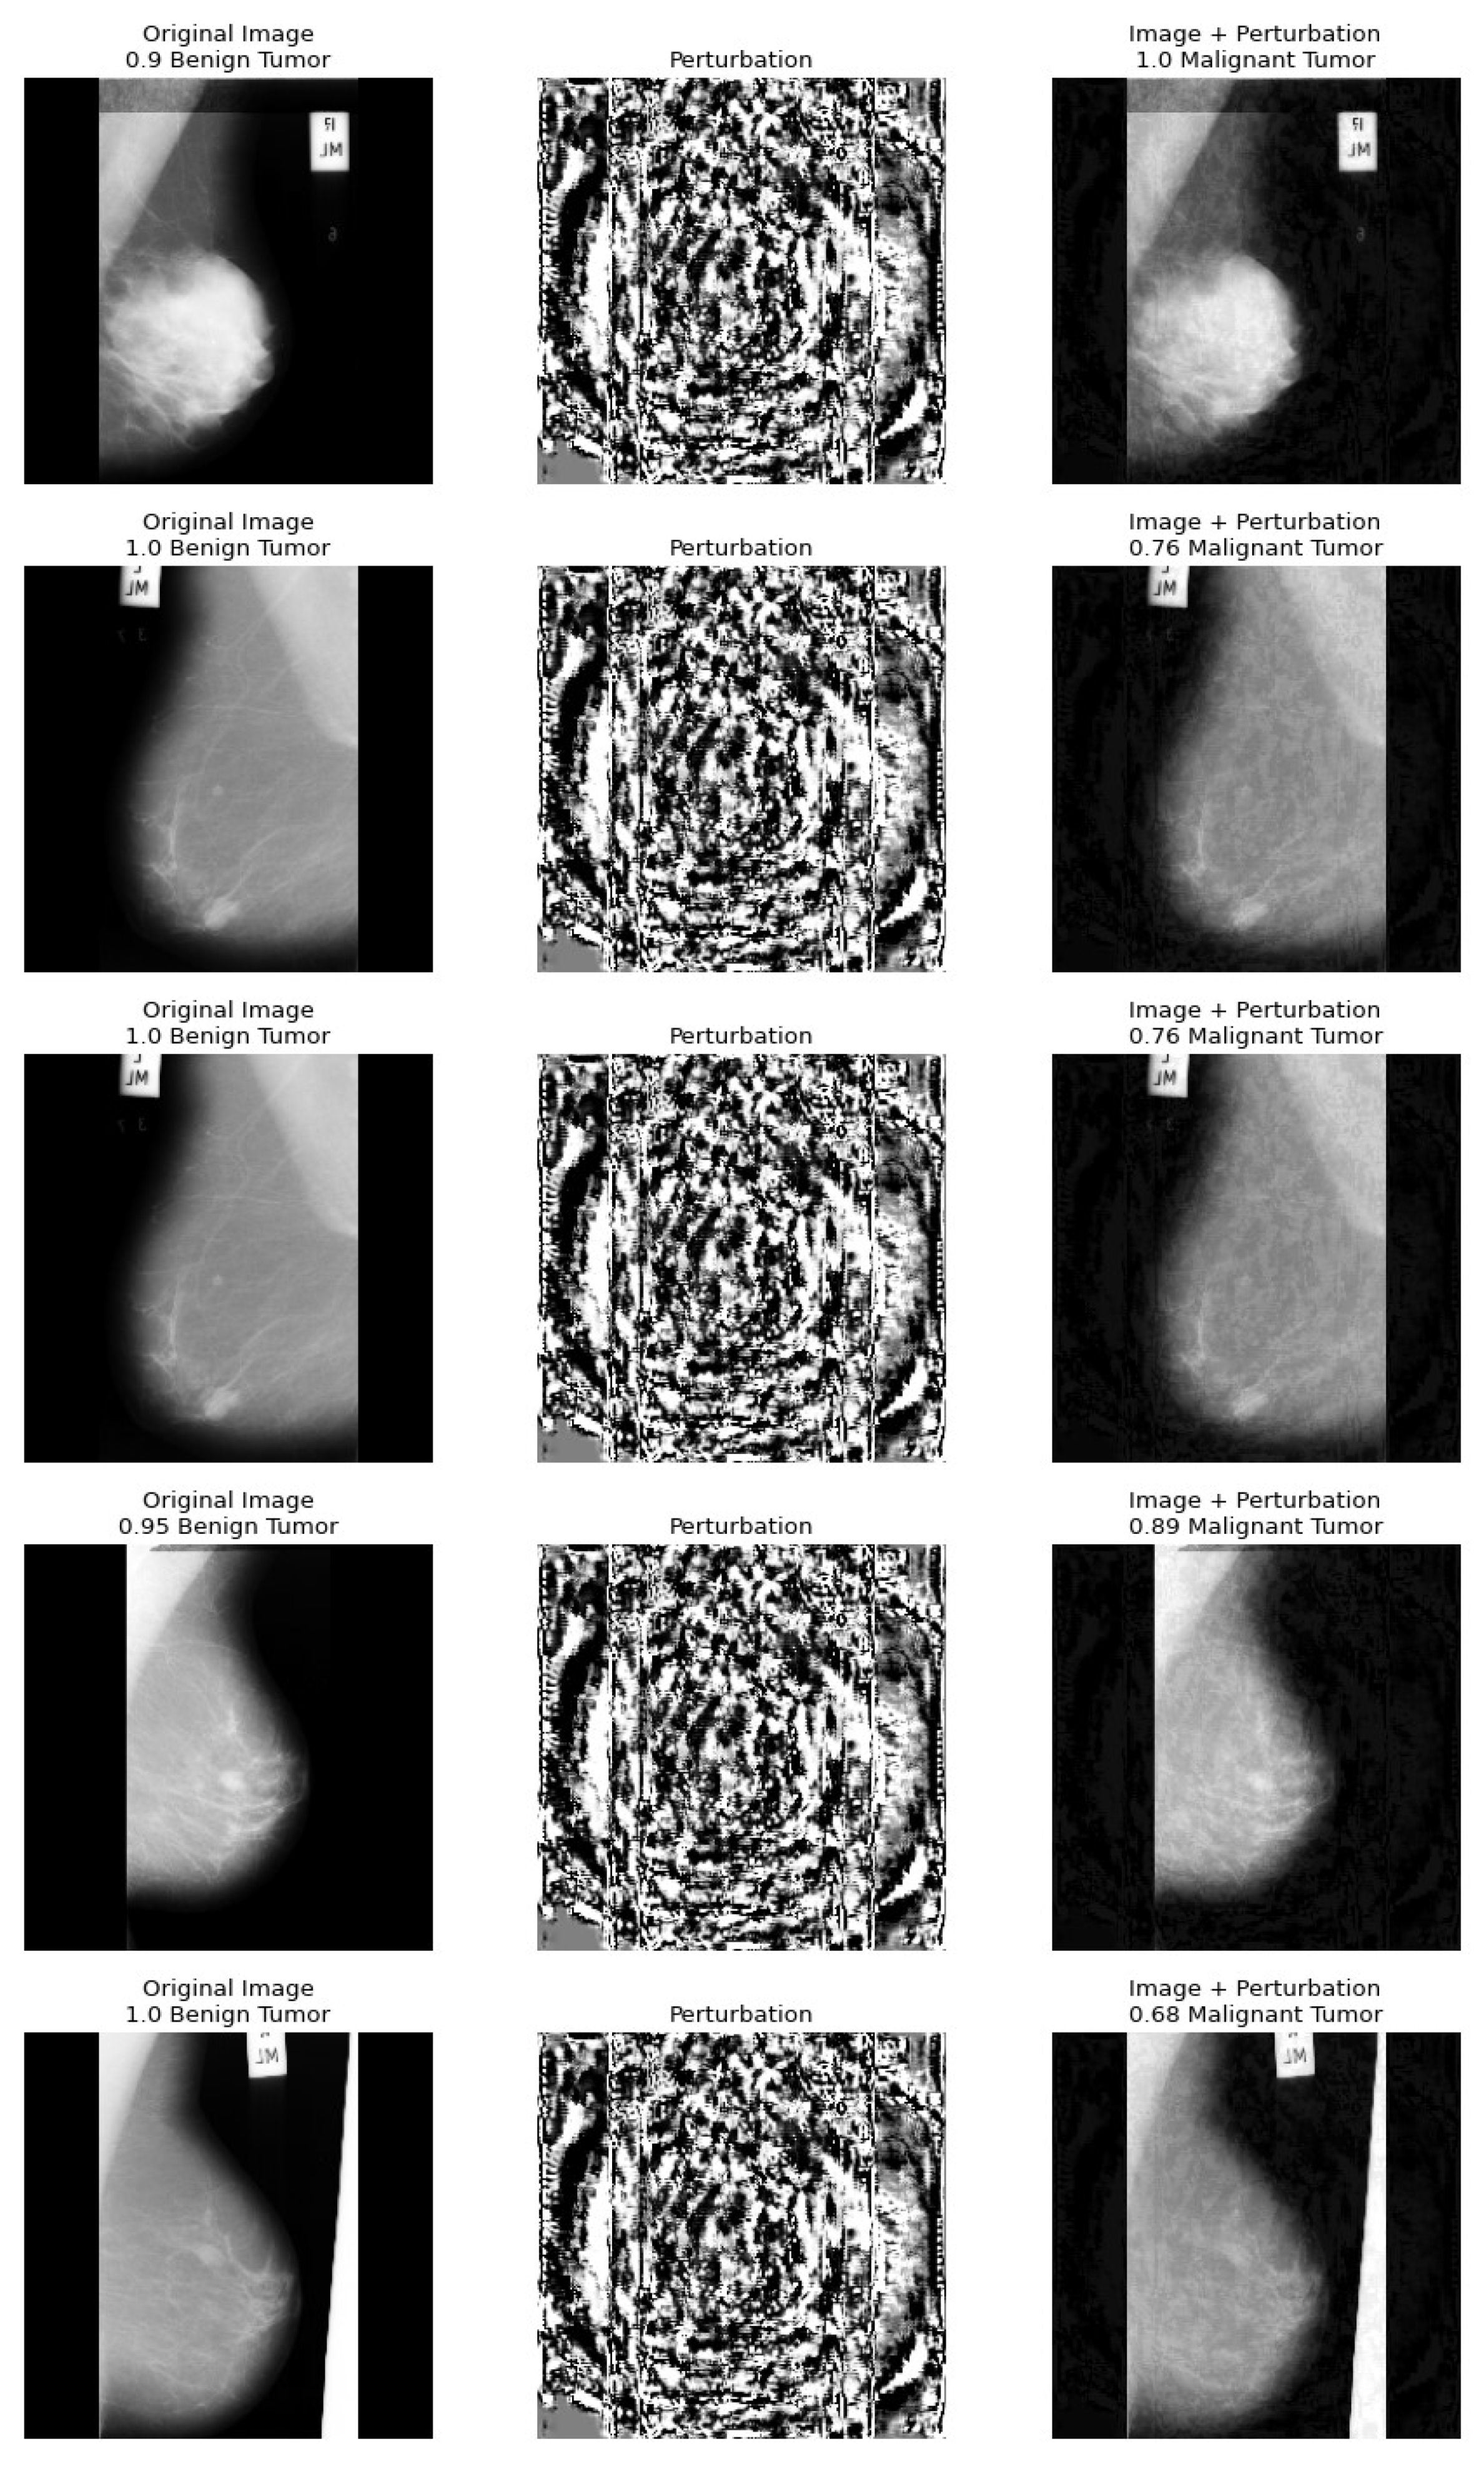

5. A Health Insurance Example and the Assessment of Damages

Dataset